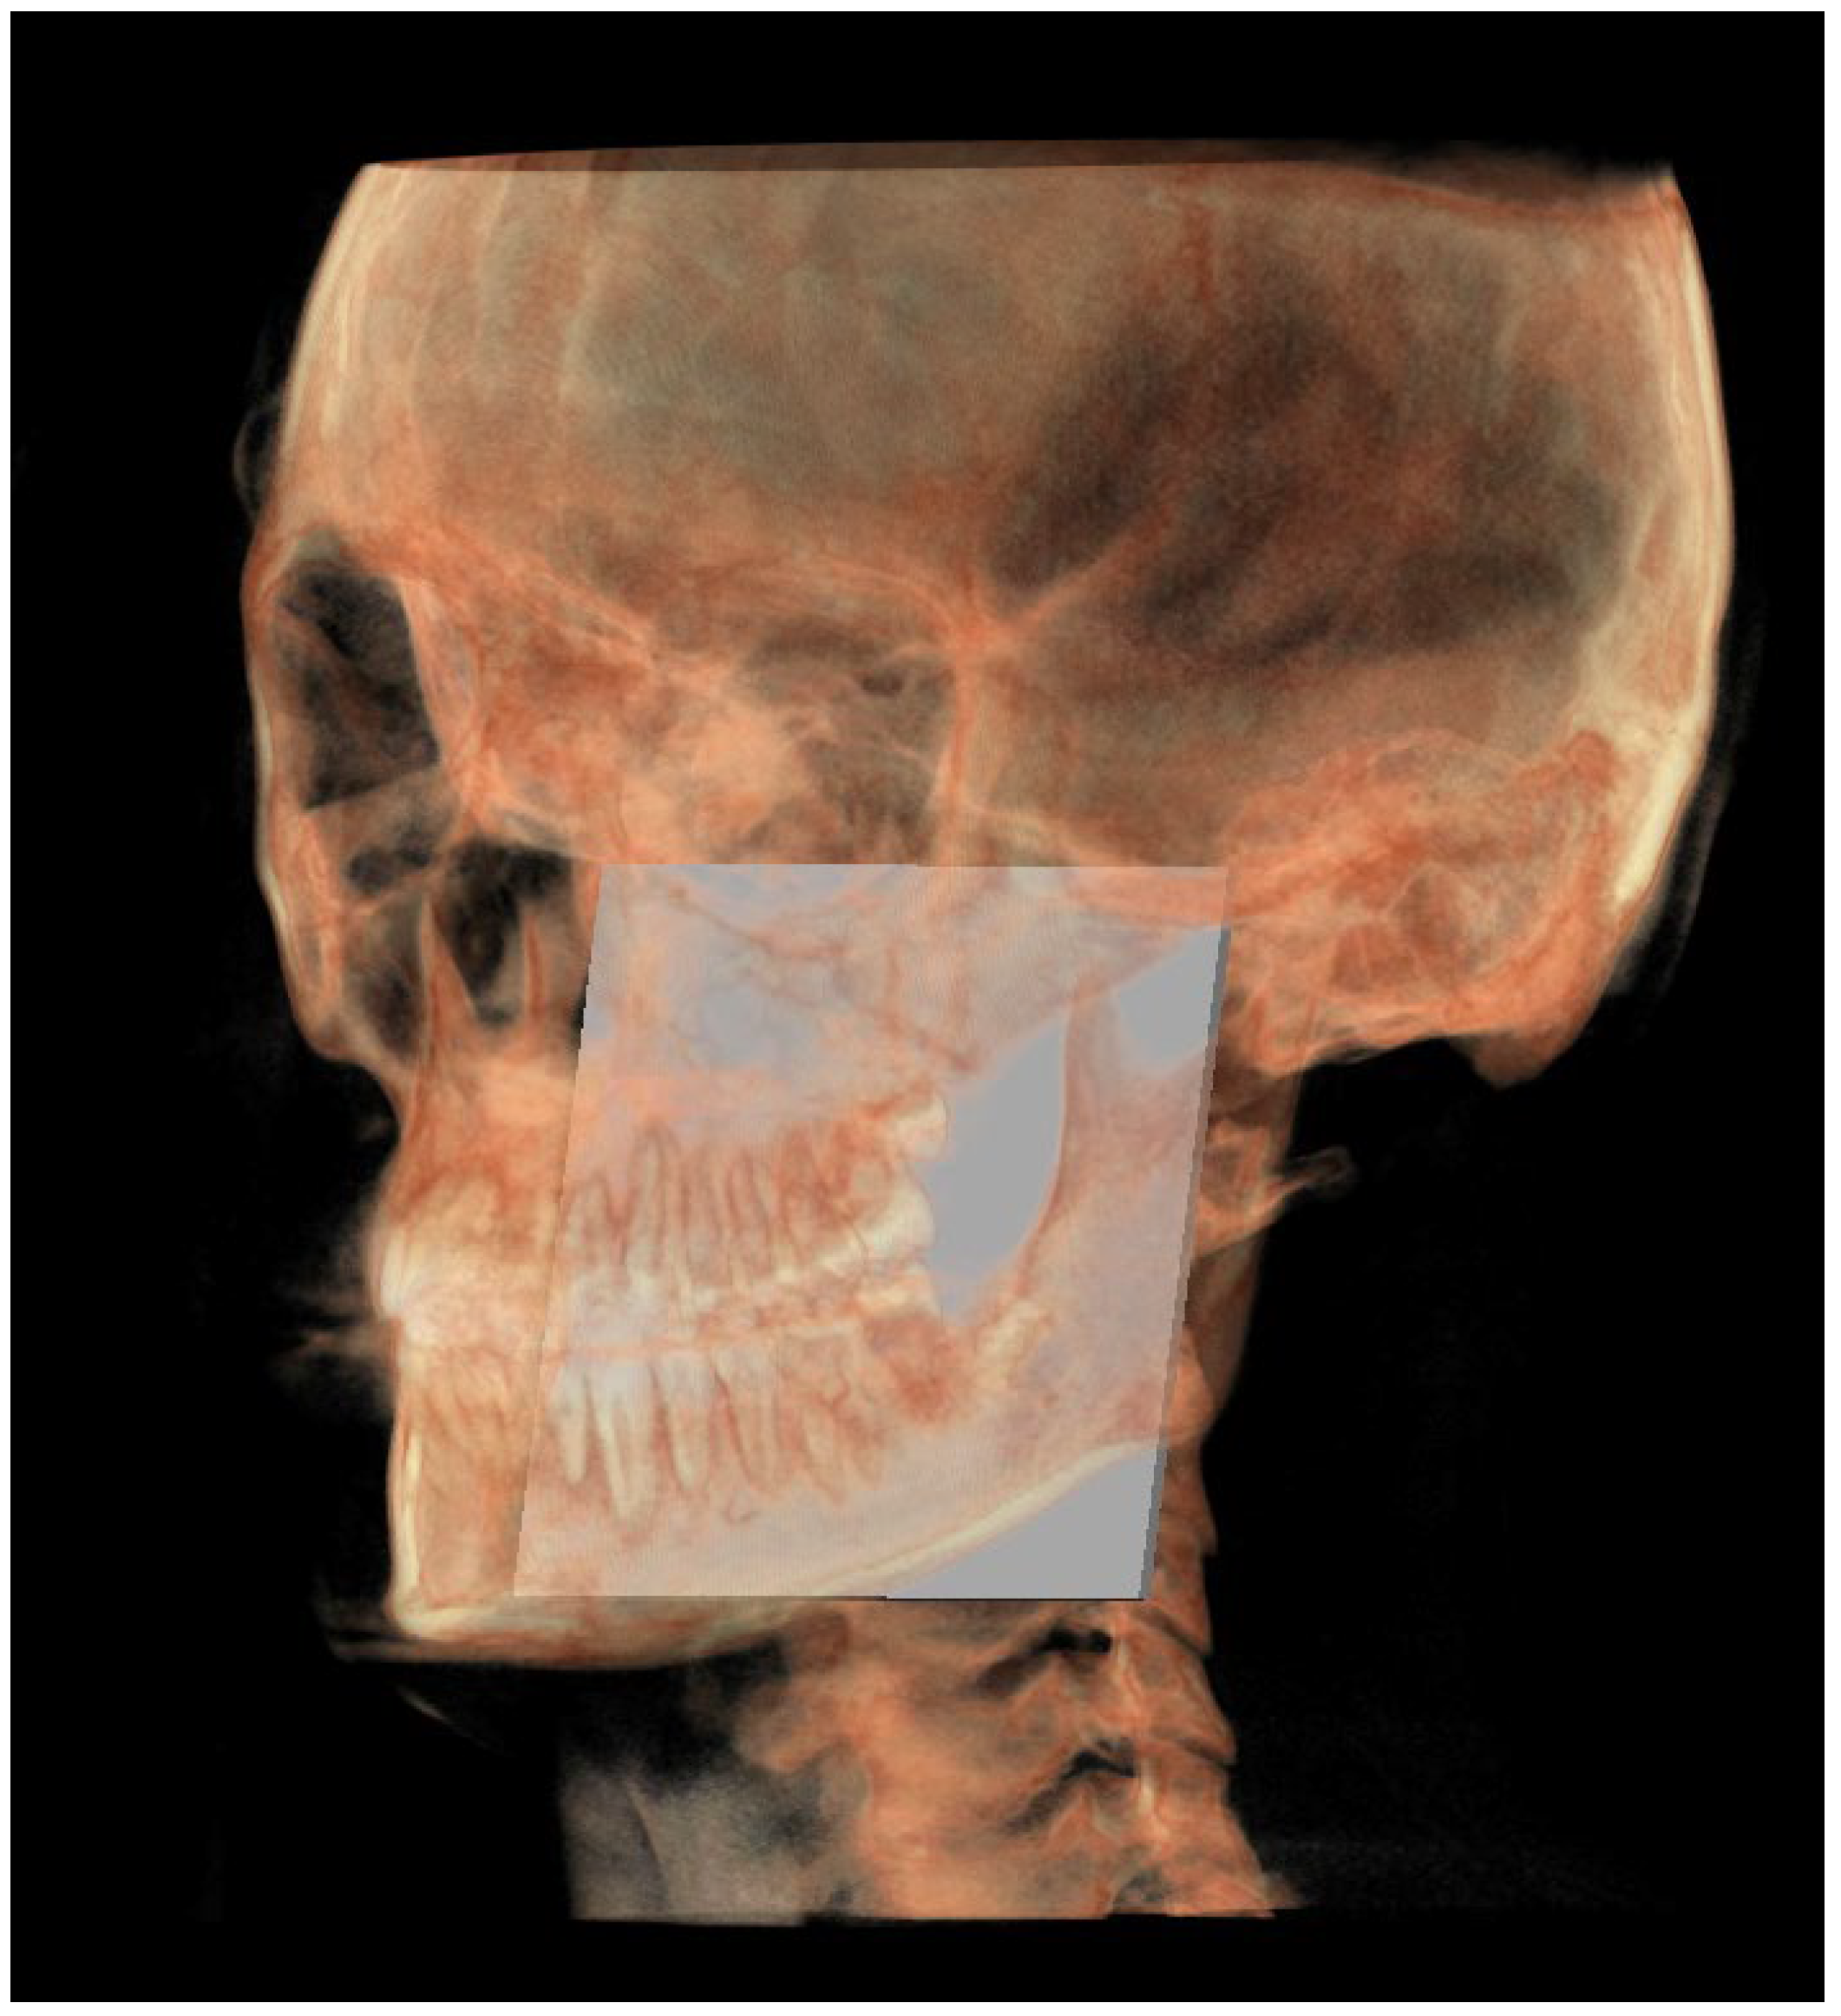

- The functional occlusal plane (FOP) (Figure 6) was identified by the posterior occlusal contact right side (rPoc), posterior occlusal contact left side (lPoc) and the middle point between the right and left anterior occlusal contact (mAoc). To adequately locate the mAoc, it is advisable to draw a line on the transversal view from the right mesial premolar contact to the left one to have a reference along which measure the distance.

| Posterior occlusal contact, right side (rPoc) | Most supero-distal contact point of the first molars, right side | / | / |

| Posterior occlusal contact, left side (lPoc) | Most supero-distal contact point of the first molars, left side | / | / |

| Anterior occlusal contact, right side (rAoc) | Most mesial contact point between the first premolars, right side | / | / |

| Anterior occlusal contact, left side (lAoc) | Most mesial contact point between the first premolars, left side | / | / |

| Middle point between right and left Aoc (mAoc) | Middle point between the rAoc and lAoc | Middle point between the rAoc and lAoc | Middle point between the rAoc and lAoc |